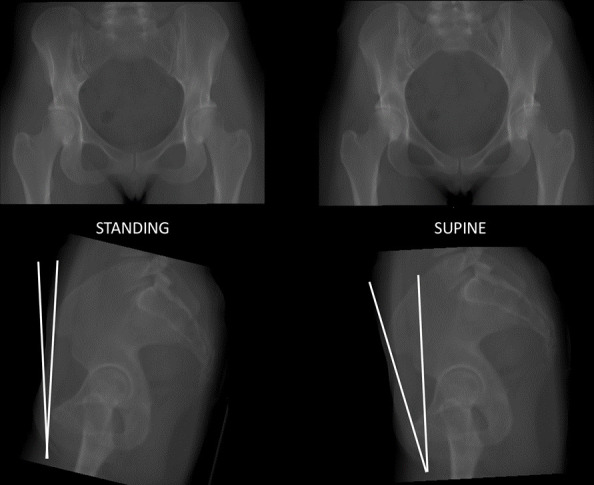

Methods: In total, 60 patients were selected from an institutional database: 20 with acetabular retroversion (AR), 20 with developmental dysplasia of the hip (DDH), and 20 with cam-type femoroacetabular impingement (FAI). Multiplanar CT reformats were created and the sagittal rotation was aligned to the APP. The sagittal pelvic orientation was then corrected until the anteroposterior (AP) projection mirrored that of their preoperative supine and standing plain radiographs. The change in sagittal pelvic tilt angle required was measured.

Results: The mean deviation from the APP in the AR group was 11.55° (SD 4.96°) for supine radiographs and 3.28° (SD 8.66°) for standing radiographs. The mean deviation from the APP in the DDH group was 12.2° (SD 4.26°) for supine radiographs and 6.96° (SD 3.43°) for standing radiographs. The main deviation from the APP in the FAI group was 8.63° (SD 5.21°) for supine radiographs and -1.28° (SD 7.31°) for standing.